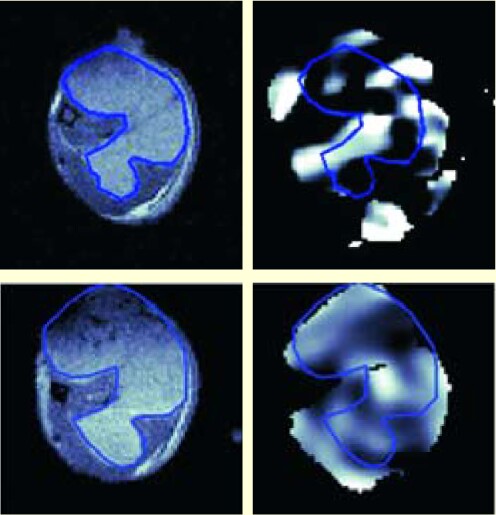

(EPRI) can determine the oxygen content of tumors and other biological tissue. Low levels of oxygen make a cancerous tumor more resistant to radiation and chemotherapy; higher doses could be administered to such areas—provided those areas could be found. With the goal of mapping biological oxygen in three dimensions, researchers at the University of Chicago are developing a new technique that lets them magnetically manipulate unpaired electrons in certain oxygen-containing molecules. With an appropriate contrast agent present, each little volume element of a sample produces an absorption line whose width gives the oxygen content at that location. The team has thus been able to quantify and image, with millimeter spatial resolution, the oxygen distribution in small animals. By superimposing those images on anatomically superior MRI images, regions rich or poor in oxygen can be located, as reported by Charles Pelizzari at the July meeting in Seattle of the American Association of Physicists in Medicine. For example, in these 7-mm panels showing a mouse tumor, the upper images were obtained just prior to a treatment and the lower ones four days later; the left images were made with MRI (with the tumor outlined); the right ones, showing a noticeable change in oxygen content (bright areas), were made with EPRI. Pelizzari thinks that images like these may have potential for biologically based planning and assessment of radiation therapy. (C. Haney et al. , AAPM Meeting talk WE-D-I-609-8. )